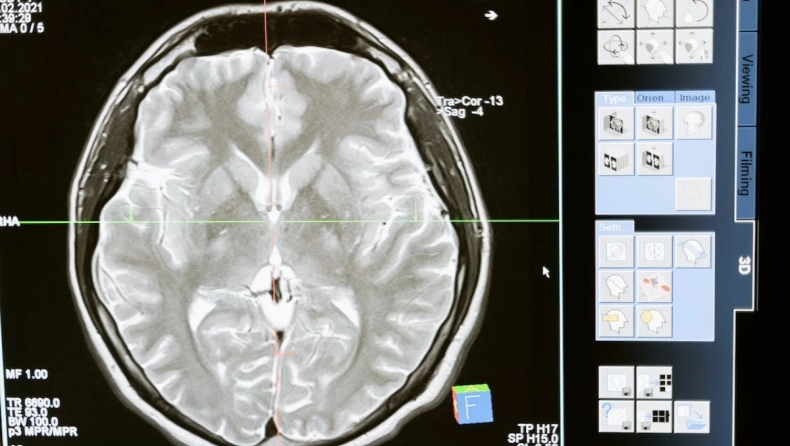

Μυστηριώδης εγκεφαλική δραστηριότητα ανιχνεύεται σε ανθρώπους λίγο πριν πεθάνουν

Το ερώτημα του τι συμβαίνει όταν πεθαίνουμε τίθεται εδώ και αιώνες, αλλά τώρα οι επιστήμονες μπορεί να είναι ένα βήμα πιο κοντά, αφού ανακάλυψαν μια μυστηριώδη αύξηση της εγκεφαλικής δραστηριότητας κατά τη διαδικασία του θανάτου.

Ειδικοί από το Πανεπιστήμιο του Μίσιγκαν παρατήρησαν μια αύξηση στην εγκεφαλική δραστηριότητα δύο ατόμων καθώς πέθαιναν - παρόμοια με την εγκεφαλική δραστηριότητα που έχει παρατηρηθεί σε ζώα των οποίων η καρδιά έχει σταματήσει.

Είναι εξαιρετικά σπάνιο για τους επιστήμονες να παρακολουθούν την ακριβή στιγμή που πεθαίνει ένας άνθρωπος. Πέρυσι, το 2022, ήταν η πρώτη φορά που τα εγκεφαλικά κύματα καταγράφηκαν με αυτόν τον τρόπο. Αυτό κατέστη δυνατό αφού ένας 87χρονος ασθενής εμφάνισε επιληπτικές κρίσεις μετά από χειρουργική επέμβαση και δυστυχώς η κατάστασή του επιδεινώθηκε. Λόγω της εντολής τους να μην επαναφέρουν τον ασθενή σε ανάνηψη, η οικογένειά του επέτρεψε στους επιστήμονες να καταγράψουν την ηλεκτρική δραστηριότητα του εγκεφάλου του.

Παρατήρησαν μια μεγάλη αιχμή στα κύματα γάμμα και σε άλλες συχνότητες για 900 δευτερόλεπτα.

Ο Ajmal Zemmar, νευροχειρουργός στο Πανεπιστήμιο του Louisville εξήγησε: «Μετρήσαμε 900 δευτερόλεπτα εγκεφαλικής δραστηριότητας γύρω από τη στιγμή του θανάτου και θέσαμε συγκεκριμένη εστίαση για να διερευνήσουμε τι συνέβαινε στα 30 δευτερόλεπτα πριν και μετά τη διακοπή της καρδιακής λειτουργίας. Λίγο πριν και μετά τη διακοπή της λειτουργίας της καρδιάς, είδαμε αλλαγές σε μια συγκεκριμένη ζώνη νευρικών ταλαντώσεων, τις λεγόμενες ταλαντώσεις γάμμα, αλλά και σε άλλες, όπως οι δέλτα, θήτα, άλφα και βήτα ταλαντώσεις».

Μια νέα μελέτη παρατήρησε παρόμοια δραστηριότητα σε δύο από τα τέσσερα ανθρώπινα όντα που βγήκαν από τη μηχανική υποστήριξη της ζωής. Οι επιστήμονες που μελετούν το φαινόμενο υποθέτουν ότι αυτή η δραστηριότητα, η οποία είναι πολύ υψηλότερη από την εγκεφαλική μας δραστηριότητα όταν είμαστε ξύπνιοι, μπορεί να συνδέεται με ανεπίσημες αναφορές όσων είχαν εμπειρίες κοντά στο θάνατο.

Η έξαρση των κυμάτων γάμμα παρατηρήθηκε σε μια περιοχή του εγκεφάλου που θεωρείται ευρέως "θερμή ζώνη" για τη συνείδηση και παρουσιάζει παρόμοια μοτίβα με αυτά που παρατηρούνται όταν κάποιος ονειρεύεται ή όταν ασθενείς που έχουν υποστεί επιληπτική κρίση αναφέρουν οπτικές ψευδαισθήσεις ή εξωσωματικές εμπειρίες.